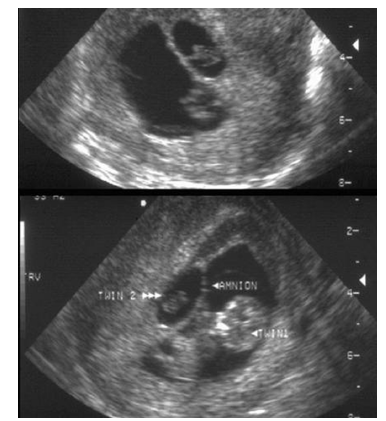

(TVS) scan on 25 July 2025 confirmed the following: This couple

at that stage (Figure 2). Similar depressive symptoms erupted

around 10th October 2025 and counselled again. The Scan report

of 18 October 25:

A. Twin live intrauterine Pregnancy

a. Twin A of GA 17 Wks. & 5 days

b. Twin B of GA 17 Wks. &

B. Liquor adequate in both the twins